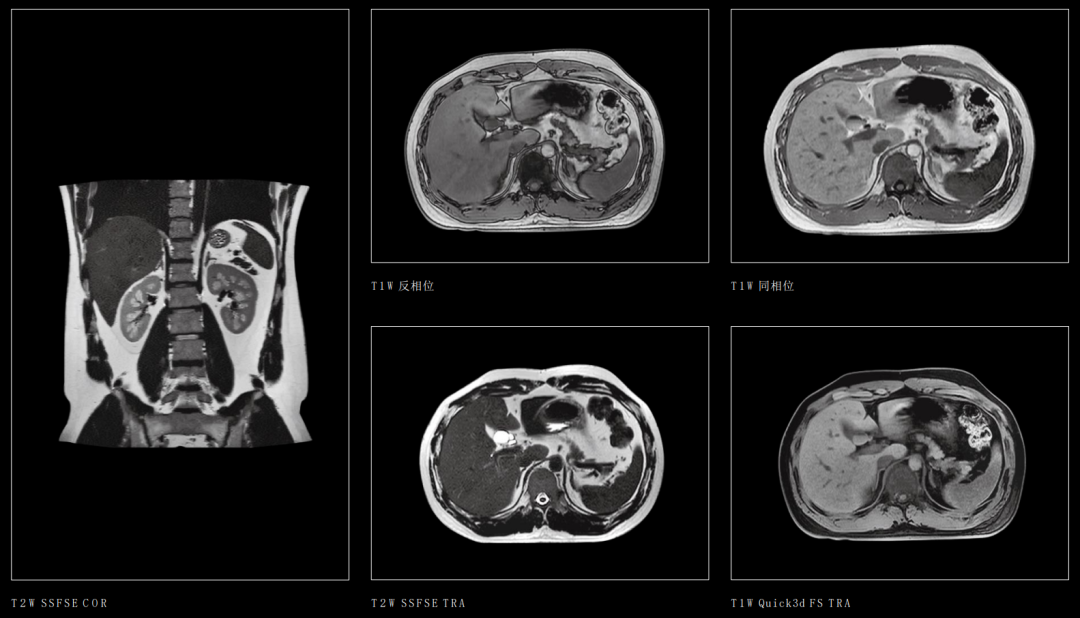

3、腹部器官

腹部良、恶性肿瘤的诊断与鉴别诊断,可以进行脂肪定量成像、磁敏感成像、腹部大血管高分辨率成像。

十二指肠壶腹部占位

肾上腺常规成像